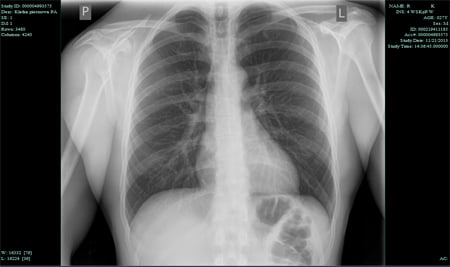

RTG klatki piersiowej jest najczęściej wykonywanym badaniem radiologicznym, które wyświetla czarno-biały obraz płuc, serca, żeber, kręgosłupa oraz naczyń krwionośnych.